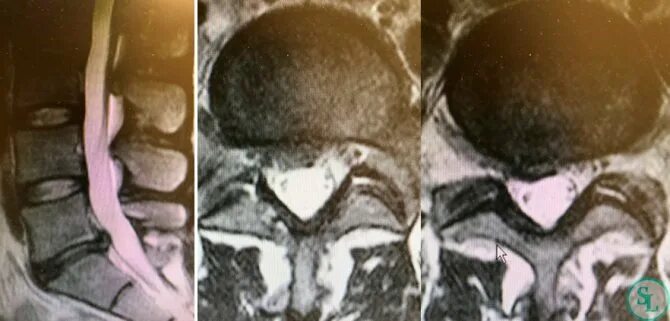

Диффузная грыжа l4 l5